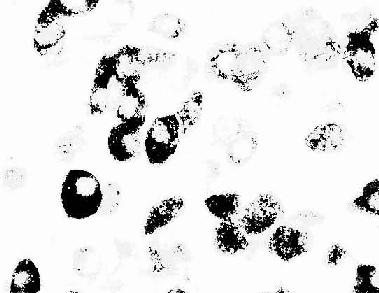

图1-6 大鼠腺垂体免疫组织化学(PAS法)示生长激素细胞

(上海医科大赵培林教授供图)

免疫细胞化学(immunocytochemistry)术是应用抗原与抗体结合的免疫学原理,检测细胞内多肽、蛋白质及膜表面抗原和受体等大分子物质的存在与分布。这种方法特异性强,敏感度高,进展迅速,应用广泛,成为生物学和医学众多学科的重要研究手段。近年随着纯化抗原和制备单克隆抗体的广泛开展以及标记技术不断提高,免疫细胞化学的进展更是日新月异,不仅用于许多基本理论的研究,并取得重大突破,而且也用于疾病的早期快速诊断等临床实际。组织的多肽和蛋白质种类繁多,具有抗原性。分离纯化人或动物组织某种蛋白质,作为抗原注入另一种动物体内,后者即产生相应的特异性抗体(免疫球蛋白)。从被免疫动物的血清中提取出该抗体,再以荧光素、酶、铁蛋白或胶体金标记,用这种标记抗体处理组织切片或细胞,标记抗体即与细胞的相应蛋白质(抗原)发生特异性结合(图1-4)。常用的荧光素是异硫氰酸荧光素(FITC)和四甲基异硫氰酸罗丹明(TRITC),在荧光显微镜下可观察荧光抗体抗原复合物(图1-5)。常用的酶是辣根过氧化物酶(horseradish peroxidase,HRP,从辣根菜中提取的),它的底物是3,3'-二氨基、联苯胺(DAB)和H2O2,HRP使DAB氧化形成棕黄色产物,可在光镜和电镜下观察(图1-6)。铁蛋白和胶体金标记抗体与抗原的结合,也可在光镜和电镜下观察(图1-7)。